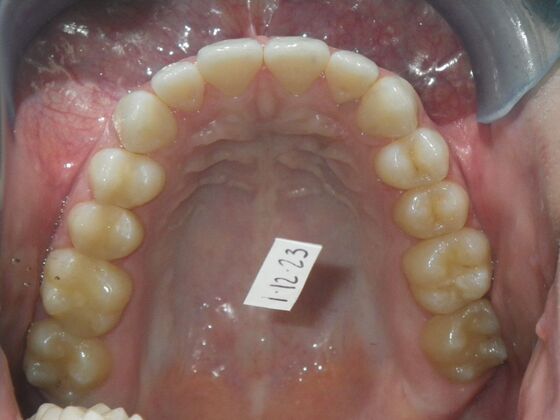

This patient was an awesome dental assistant for our practice and we were all very sad when she had to move closer to her home. She was very interested in correcting some minor spacing and rotations in her upper and lower anterior teeth and to decrease her overbite as well.Treatment took about 12 months, but we were pleased with the results and fabricated clear invisalign vivera retainers. We are still hoping one day she will return to be with us again.